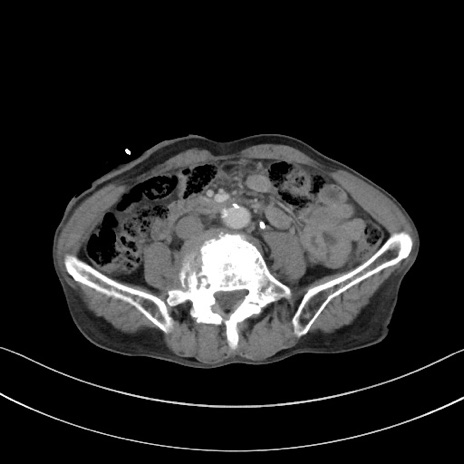

症例3(横断像)

【症例】 70歳代男性

【主訴】右鼠径部腫瘤、疼痛

【現病歴】本日朝より上記主訴あり、受診。

【既往歴】膀胱癌にて膀胱全摘、両側尿管皮膚瘻

【データ】WBC 5600、CRP 0.56